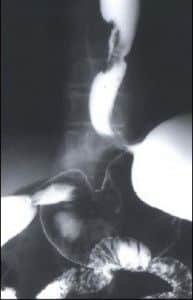

HERNIAS

• DE HIATO